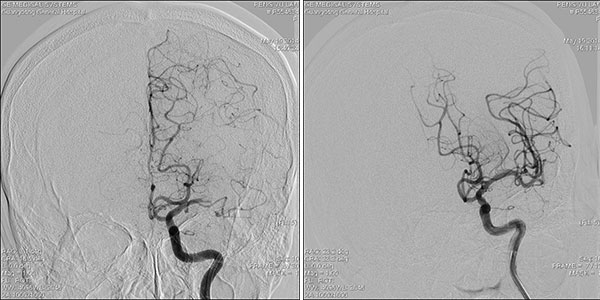

病例2 今年5月彭奶奶突发不能说话,右侧手脚不能动弹,考虑为脑血管意外,即急行头颅CT考虑为脑栓塞,转送介入室,由神经内科王硕主任团队紧急为患者进行取栓术,脑动脉栓塞部位(图4),取出栓子(图5),栓塞脑动脉恢复血流(图6)。患者痊愈出院。

图4 取栓前,左侧大脑中动脉闭塞 图6 取栓后,右侧大脑中动脉血流再通

图5 取出血栓